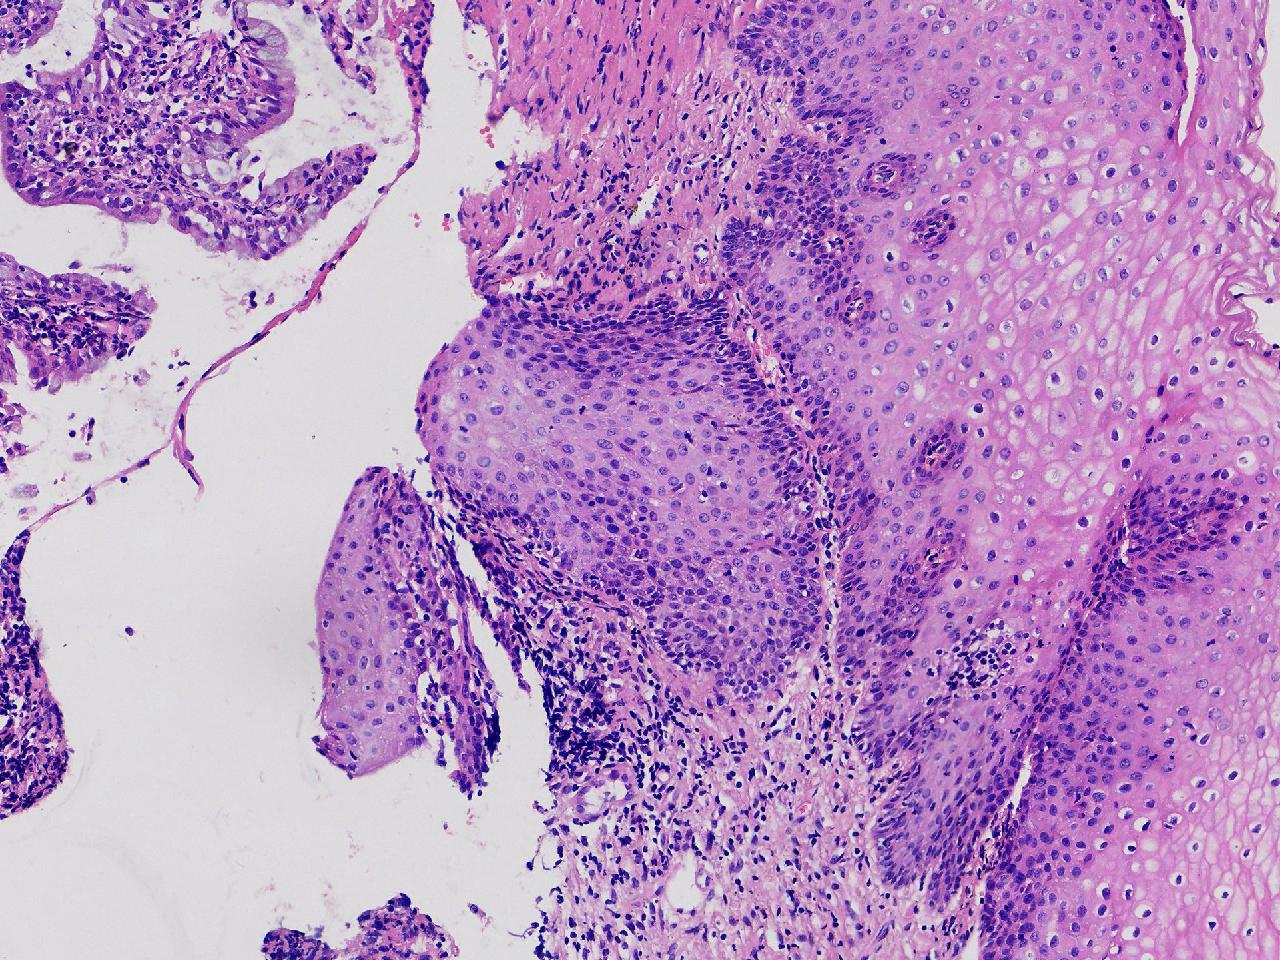

此处鳞化腺体够不够CIN1级? 应该不到CIN2级吧?

性别

女

年龄

47岁

临床诊断

宫颈活检组织

一般病史

宫颈活检,HPV不详。

标本名称

宫颈活检

大体所见

宫颈活检组织。

图1

图2

图3

图4

鳞化

二级没有,好像有hpv感染,如果有hpv高危阳性,建议低度